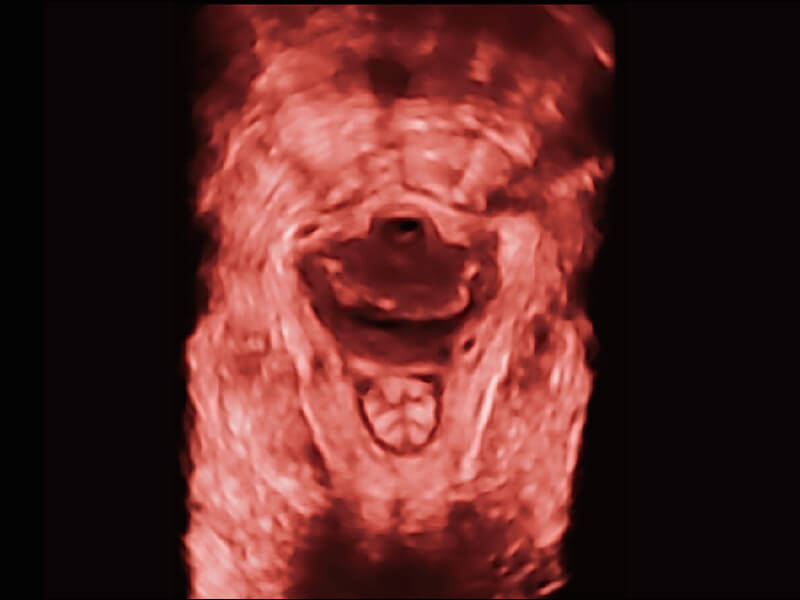

创新的超宽频带技术,为容积成像带来优质的二维图像基础,为您呈现更丰富的结构细节,栩栩如生地展示宝宝的宫内形态以及各种组织的立体结构。